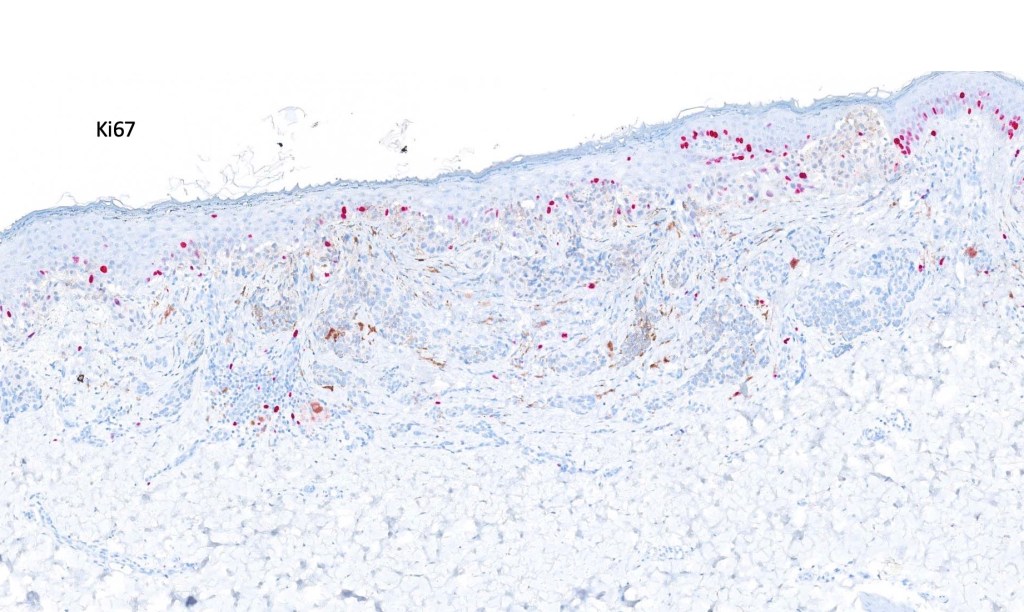

. HMB45 shows gradation with depth, Ki67 is low